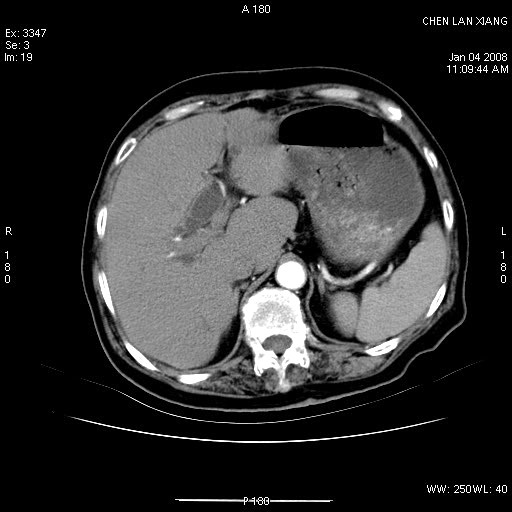

女,76岁,腹痛3-4天,b超示:肝内实性肿物,胆囊强回声,胆总管扩张.

考虑:1、胆总管下端结石伴梗阻性肝内外胆管扩张(肝左叶外侧段肝内胆管多发结石、胆管炎);

2、肿囊癌累及肝,不除外 黄色肉芽肿性胆囊炎。

1 胆总管末端结石伴肝内胆管结石,肝内外胆管扩张。2 胆囊扩大,胆囊壁不规则增厚,内见软组织密度影。考虑:慢性胆囊炎,不除外胆囊癌!

ct所见:1、 肝内胆管结石,肝内外胆管扩张。低位胆道梗阻,胆总管下端结石;2 胆囊扩大,胆囊壁不规则增厚

考虑:胆总管下端结石并肝内外胆管扩张,肝内胆管结石;

慢性胆囊炎

1)胆囊癌伴肝脏转移。2)胆总管下端结石、肝内胆管结石伴肝内外胆管扩张。